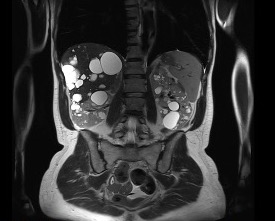

Resonancia magnética hepática: confirmación definitiva

Para completar la caracterización, se realiza resonancia magnética hepática.

Los hallazgos son muy ilustrativos:

- Gran cantidad de quistes hepáticos y renales

- En secuencias T2: lesiones marcadamente hiperintensas (muy brillantes)

- En el plano coronal: ocupación extensa del parénquima hepático y renal

La RM confirma de forma elegante la naturaleza quística de la mayoría de las lesiones.